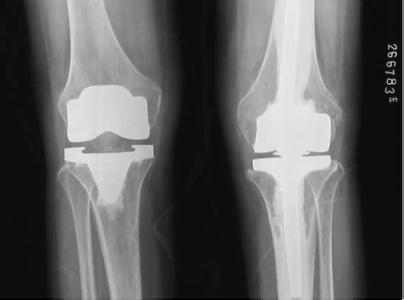

貴陽強(qiáng)直醫(yī)院風(fēng)濕性關(guān)節(jié)炎CT 檢查

(圖:風(fēng)濕性關(guān)節(jié)炎的CT檢查)

3、關(guān)節(jié)影像檢查:大家如果懷疑自身患上了這種疾病,應(yīng)該進(jìn)行這種檢查,X線檢查有助于關(guān)節(jié)病變的診斷和鑒別診斷,亦能隨時(shí)了解關(guān)節(jié)病變的演變,是目前常用的影像學(xué)診斷方法。